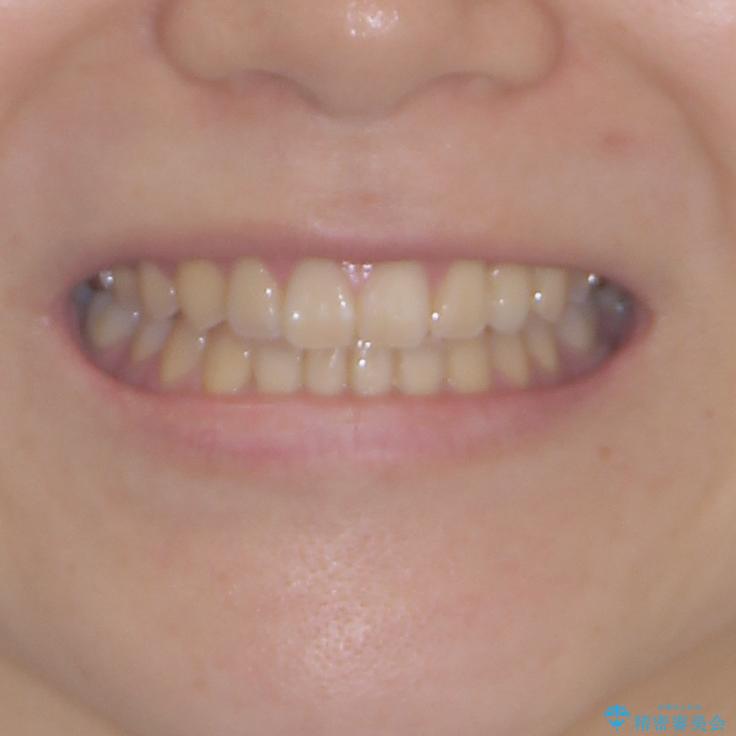

- 前歯の開咬と、受け口による咬み合わせの悪さを気にして来院された患者様です。

上顎歯列が狭窄していたため、急速拡大装置により上顎骨を側方に拡大し、その後インビザラインにて矯正治療を行うこととしました。

インビザラインの装着時間が不十分であったので、治療期間は長期間となりました。